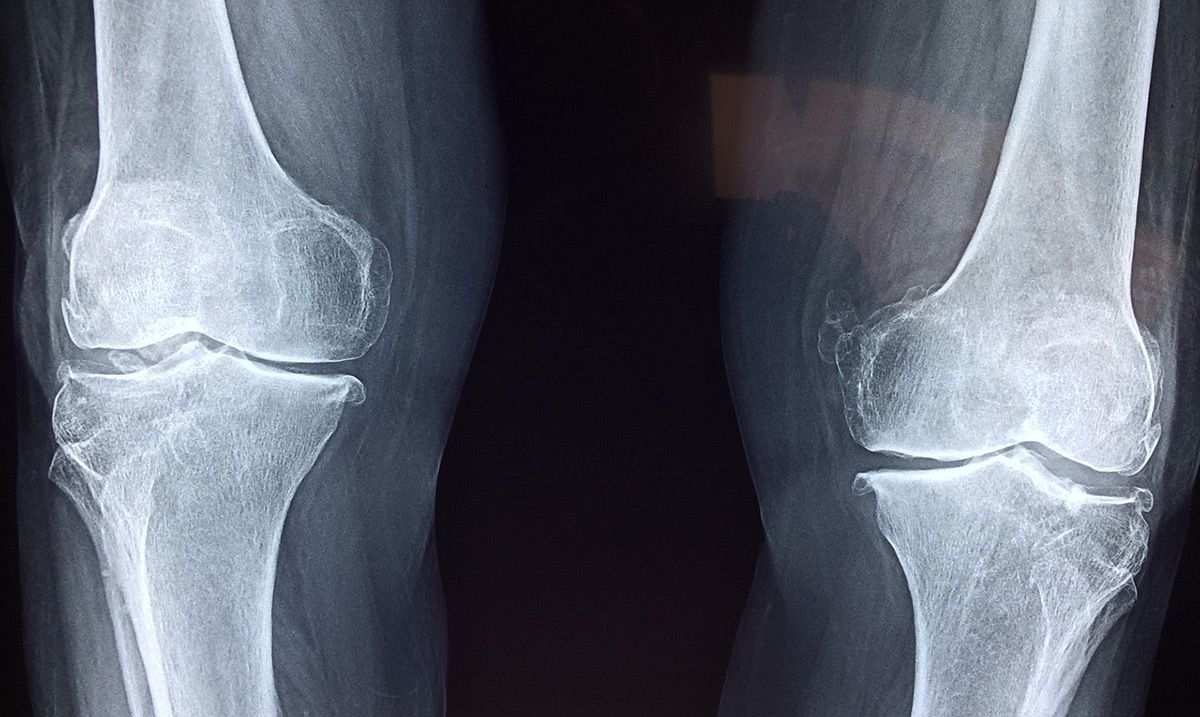

La práctica deportiva es la base de un modo de vida saludable. Sin embargo, las lesiones de rodillas son comunes entre quienes realizan deporte de manera asidua. Además de tratamientos con especialistas, los afectados por estas lesiones deben recurrir a consejos y productos que alivien el malestar causado por el dolor o la incomodidad, como aplicación de hielo o un gel de masaje para articulaciones.

Salvo contadas excepciones, las lesiones de rodillas son corrientes y se solucionan con un diagnóstico acertado y un tratamiento adaptado a las circunstancias. Por ello, no debe cundir el pánico si en alguna ocasión se perciben pinchazos o molestias.

Las lesiones de rodilla más comunes